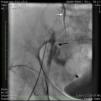

An angiogram from the left femoral sheath at this time showed retrograde filling of the distal and proximal SFA (Figure 4) and then the dissection plane in the EIA with a wire tip perforation and bleeding (Figures 5 and 6) to the retroperitoneal region at the external iliac artery with displaced bladder (Figure 6). Protamine was given to reverse the heparin and a 7-minute balloon inflation was performed in the distal SFA using a 5.0 mm×40 mm Evercross balloon (ev3, Plymouth, MN) to stop the retrograde bleeding. On repeat angiography, the distal SFA CTO was reoccluded and the dissection plane appeared to be sealed, with no further bleeding into the retroperitoneal region (Figures 7 and 8). Other than mild nausea after protamine, the patient reported no major symptoms during this procedure. When activated coagulation time was 130 s, the femoral and popliteal sheaths were removed. A 3-g/dl drop in hemoglobin was noted after the procedure that remained stable over the next two days. Popliteal and pedal pulses were palpable and unchanged following the procedure.